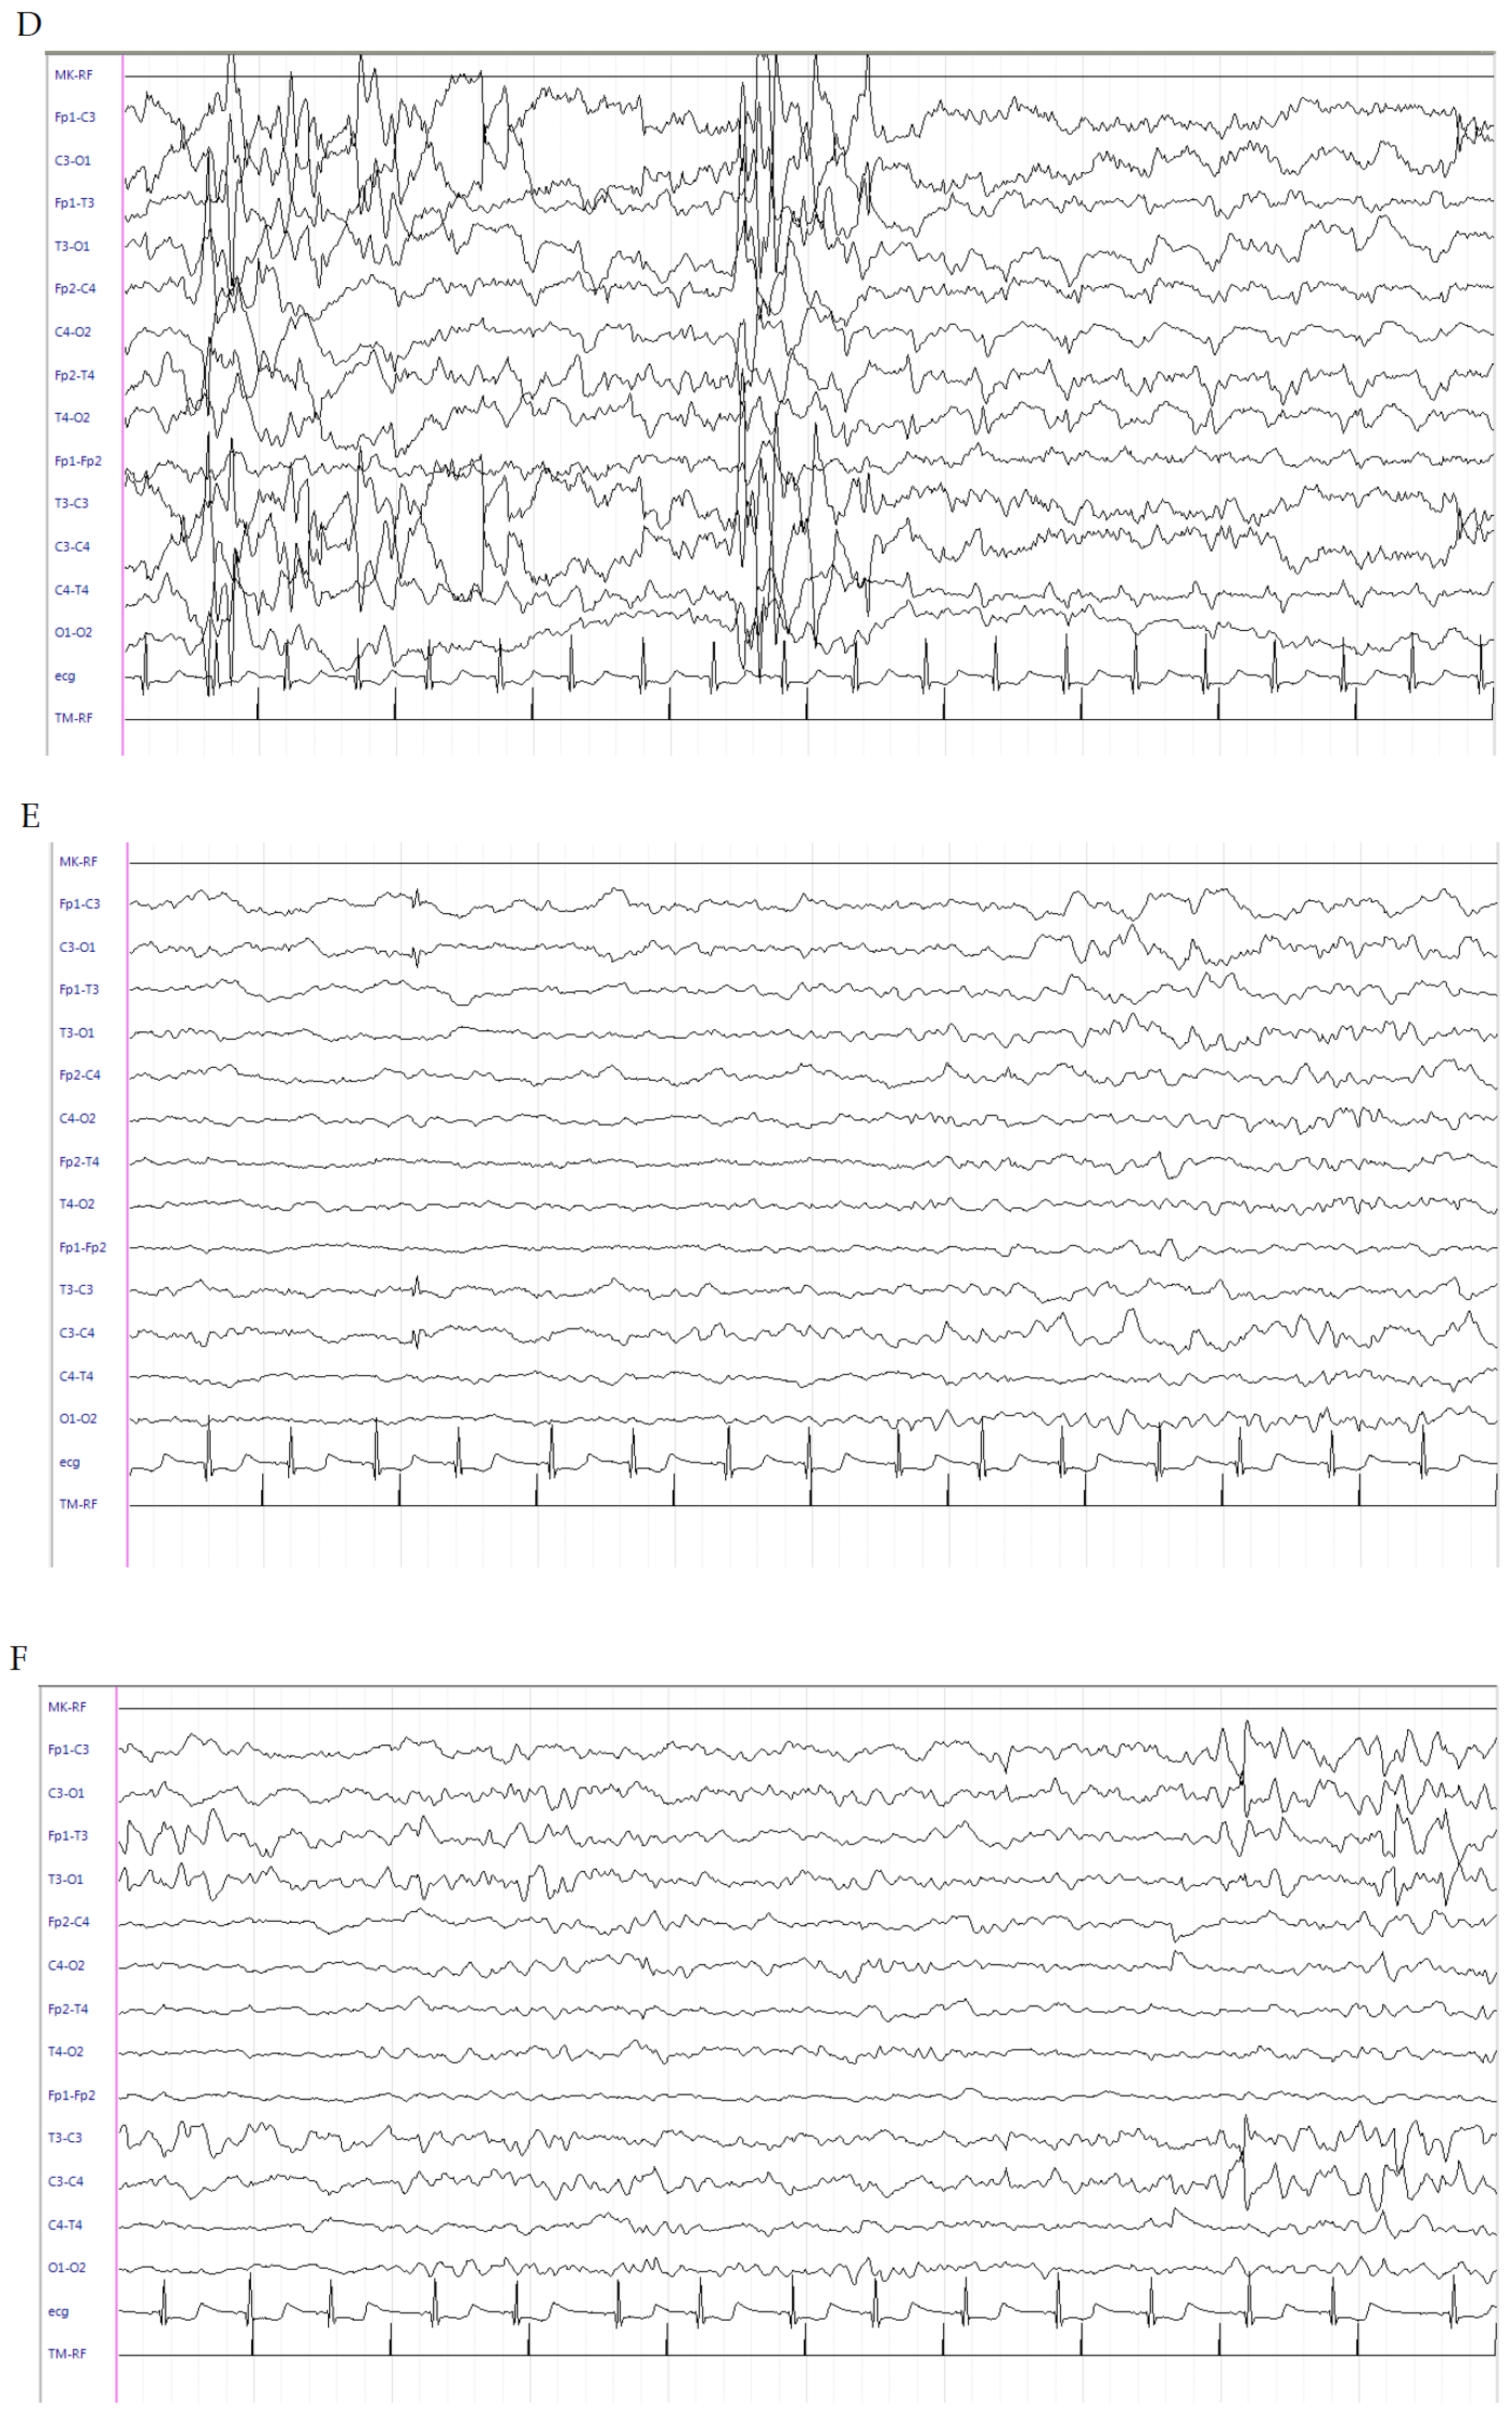

This is a male patient born at the 324/7 weeks of GA from pregnancy complicated by threatened abortion since the 21st week of gestation and requiring a cesarean section due to premature rupture of membranes. Apgar score was 7 at 1 min and 9 at 5 min. Birth weight was 1760 g (50th percentile). On the 1st day of life, due to the appearance of left pneumothorax, thoracic drainage was positioned and the baby was admitted to the NICU of our hospital. Noninvasive ventilatory support was maintained with subsequent treatment with surfactant. EV dopamine and adrenaline were administered. However, due to worsening of respiratory conditions, he was intubated. Laboratory tests revealed metabolic acidosis (pH 7.19, PCO2 41.7 mmHg, PO2 49.9 mmHg, EB -12 mEq/L, HCO3 15.4 mEq/L). CUS scan failed to reveal structural abnormalities. Since day 16, daily recurrent seizures (1–2 times/h) appeared with bradycardia, sucking automatisms, clonic jerks and hypertonia to the four limbs, lasting for several seconds. LEV as a bolus was administered (40 mg/kg) and subsequently maintained at 10 mg/kg/dose three times daily. Midazolam as a continuous infusion was gradually uptitrated to 2 mcg/kg/min. Upon neurological examination, the patient was extremely hypotonic with persistent sporadic clonic movements at the four limbs and dystonic posturing elicited by mild tactile stimulation. The EEG showed multifocal epileptic discharges (Figure 3A). Despite the persistence of seizures, due to the severe hypotonia and lethargy of the newborn with frequent ictal bradycardia, PB and PHT treatments were avoided. At this time, hydrocortisone was started (5 mg/kg). A gradual reduction until the disappearance of clinical seizures was observed after 2 days of therapy, and midazolam was gradually suspended. The ictal EEG was characterized by onset of medium-voltage, rapid, spiky activity in bilateral central regions followed by medium–high-voltage generalized polyspike discharges (Figure 3B). No clinically evident seizures have been detected since. Brain MRI scan at the corrected age (CA) of 35 + 4 weeks showed multiple ischemic lesions affecting bilateral subcortical and periventricular white matter with interspersed cavitations. The patient started a gradual decrease of hydrocortisone until withdrawal at 38 weeks (CA). At this age, he was seizure-free and the interictal EEG during quiet sleep recorded at 38 weeks CA showed periodic brief sequences of variable activity, low-voltage, alpha-like activity in the central regions, tracts of diffuse background attenuation and high-voltage, sharp waves in the central regions. No epileptiform discharges were evidenced (Figure 3C). LEV at 60 mg/day was continued. Neurological examination showed a remarkable improvement of the alertness; in contrast, moderate axial hypertonia and poor pattern of general movements were persistently observed.

Figure 3.

Electroencephalogram (EEG) of patient 3. (A) Multifocal medium–high-voltage generalized polyspike discharges. (B). Ictal EEG characterized by onset of medium-voltage, rapid, spiky activity in bilateral central regions followed by medium–high-voltage generalized polyspike discharges (C). Interictal EEG during quiet sleep recorded at 38 W CA, showing periodic brief sequences of variable activity; low-voltage, alpha-like activity in the central regions; tracts of diffuse background attenuation; and high-voltage sharp waves in the central regions. No epileptiform discharges were evidenced.